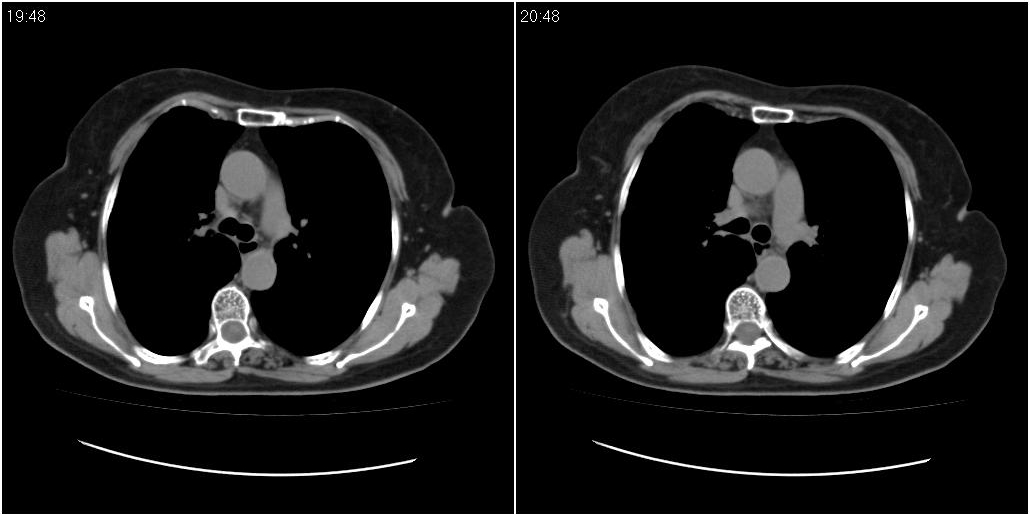

女性,72岁。去年9月份发现肺部病变,诊为肺结核并进行正规治疗至今,但复查后发现ct表现几乎没有变化。

右侧中叶支气管明显狭窄,建议行纤支镜检查!

右中间段支气管局限性狭窄,右中叶支气管亦稍显狭窄,但并未见明显占位表现,半年多了,无变化也许是好事,可能为炎性狭窄,建议继续随访。

右中叶炎性改变,支气管狭窄但较光滑,占位可能性不大。

右中间段支气管局限性狭窄,右中叶支气管亦稍显狭窄.